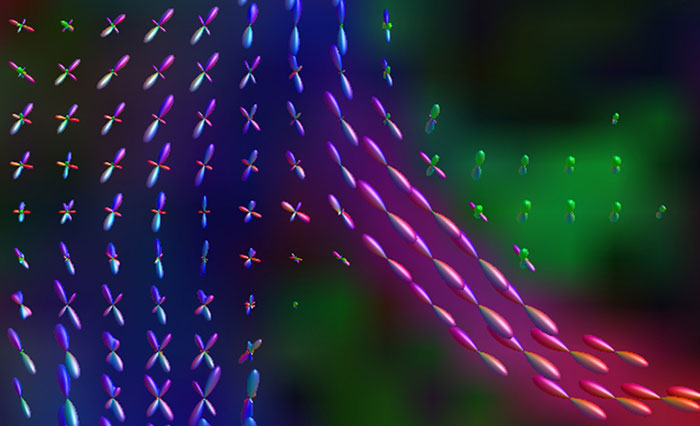

Advancing diffusion MRI

These images are produced using the ABCD protocol and illustrate the use of more sophisticated and accurate models of diffusion. The color FA maps are shown for reference. The diffusion tensor model represents the diffusion within each voxel as an ellipsoid.

Alternative models, such as constrained spherical deconvolution, better capture the rich information available with the use of high b-value dMRI and many sampling directions. In much of the brain, voxels contain multiple white matter tracts, and it is essential to capture this information to be able to perform accurate tractography and generate diffusion connectomes.

Diffusion acquisition on Achieva 3.0T dStream with matrix 140x141, 81 slices, FOV 240x240 mm, voxels 1.7x1.7x1.7 mm, TR 5300 ms, TE 89 ms, flip angle 78, MultiBand SENSE factor 3, partial Fourier 0.645, 102 diffusion directions, b-values 0 (6), 500 (6), 1000 (15), 2000 (15), 3000 (60) , scan time 2x 4:37 min. Images provided by Dr. Watts.